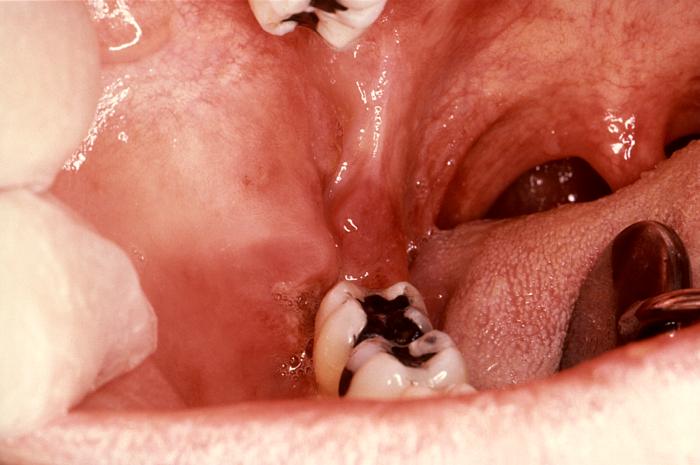

Esta neoplasia a veces presenta un

aspecto tumoral, pero muchas veces se observa como una mácula rojiza, en el

primer caso tiene un peor pronóstico.

Este tumor es multifocal y

en la boca puede observarse varias lesiones en paladar y/o encía, aunque lo

más frecuente es que el paciente tenga otras lesiones en piel de

extremidades superiores, torax

y cara.

Sarcom de Kaposi

en zona de trígono retromolar |